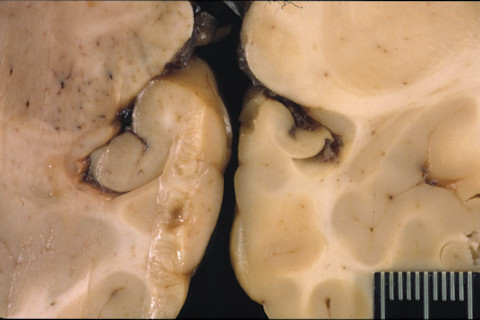

Hippocampal lesions in the sea lion brain from natural exposure to domoic acid. (Credit: The Marine Mammal Center) “We knew there was some degree of brain damage in a lot of animals [exposed to domoic acid], but if it was only a little brain damage maybe that wouldn’t be that big a deal,” says Cook. “But what we saw, which really wasn’t known, was that with progressive damage these animals were really losing most of their spatial memory faculty – and that is not a good thing if you’re a complex forager who lives in a large environment.” Cook published his findings Monday in the journal Science.